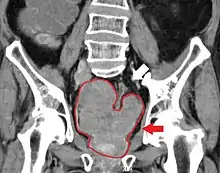

In patients who received combined treatment with Docetaxel, four of sixteen patients experienced dose-limiting toxicities at 640 mg:[4]

- Dyspnea

- Pleural effusion